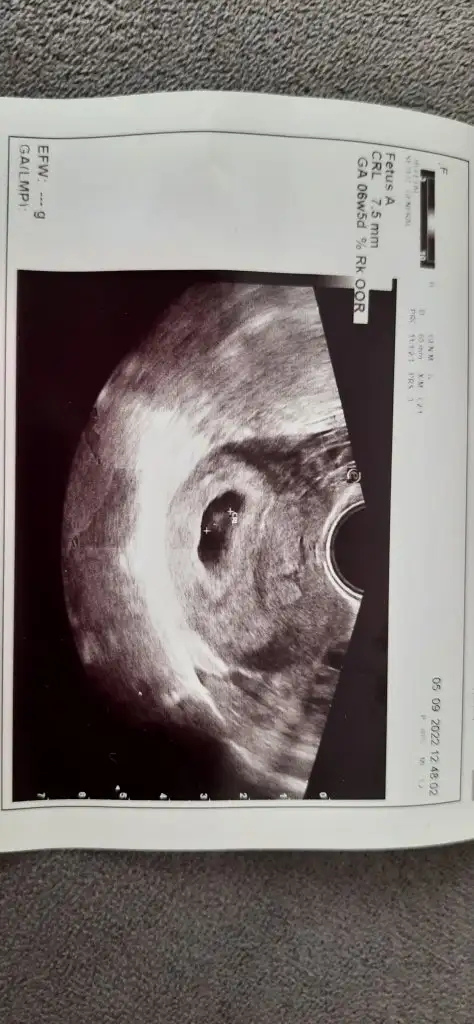

Kızlar ben kontrolden geldim karından baktılar hem bebeği hem kalp atışını gördüler ama doktor çok emin olamadı kalp atışından bide vajinal bakmak istedi vajinal bakınca daha net bir şekilde kalp atışı var dedi çok şükür cihazları zayıf olduğundan sanırım biraz görüntü kalitesi bozuk ama yine de atayım yorumlarınıza açığız 🤗😍

Ramzi teorisine göre kız duruyo, bakalım çıkacak mı 😍